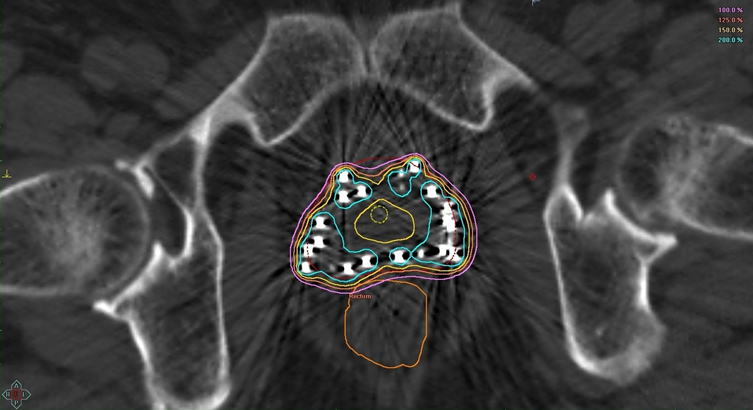

前立腺内の線量分布の確認